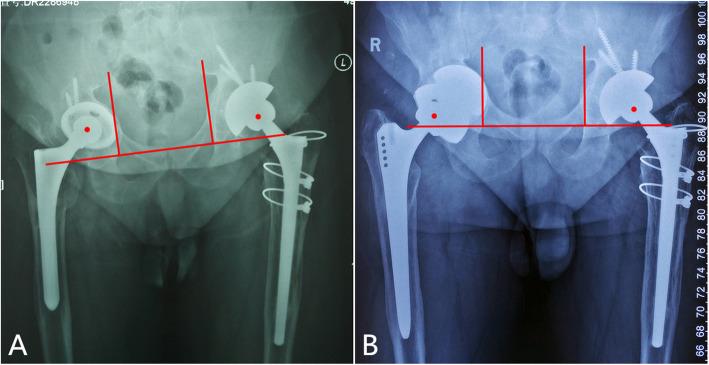

Between January 2015 and December 2018, the multicup reconstruction was performed in 21 patients with severe protrusio acetabular defects. The revision shell, plus two similar porous acetabular components was implanted into the initial shell to create a "multicup" construct. The functional outcomes were evaluated in terms of the Harris Hip Score. Acetabular loosening, restoration of hip center of rotation, and bone ingrowth etc., were radiographically assessed. The survival rate of the implants was also evaluated.

A followup lasting a mean time of 31 months (range, 18-57 months) revealed that the average Harris Hip Score improved from preoperative 37.0 ± 7.1 to postoperative 76.4 ± 9.0. There were no revisions due to acetabular loosening. The horizontal offset increased by an average of 14 mm, and the vertical offset decreased by an average of 18 mm. Eighteen of the 21 patients (86 %) met at least 3 of 5 criteria associated with bone ingrowth. The survivorship free from re-revision for acetabular loosening after 2 years was 100 %.

2015年1月至2018年12月期间,对21例髋臼严重内陷缺损患者进行多杯重建。将翻修髋臼杯与另外两个类似的多孔髋臼部件植入初始髋臼杯中,构建“多杯”结构。根据Harris髋关节评分评估功能结果。通过影像学评估髋臼松动、髋关节旋转中心的恢复以及骨长入等情况。同时评估植入物的生存率。

平均随访31个月(范围18 - 57个月)显示,Harris髋关节评分平均从术前的37.0±7.1提高到术后的76.4±9.0。没有因髋臼松动而进行翻修的病例。水平偏移平均增加14 mm,垂直偏移平均减少18 mm。21例患者中有18例(86%)至少满足与骨长入相关的5项标准中的3项。2年后因髋臼松动无需再次翻修的生存率为100%。